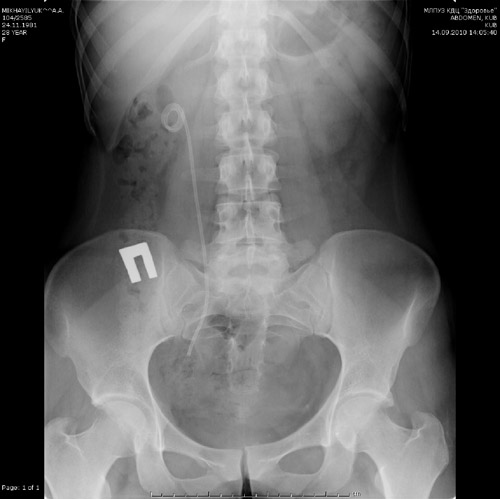

На трех рентгенограммах показаны установленные модифицированные стенты при различных клинических ситуациях.

С 2005 года в хирургическом отделении КДЦ «Здоровье» более чем 350 пациентам были установлены модифицированные нами стенты. Мы решили изменить форму double-pigtail стента на модифицированный нами mono-pigtail стент - отличительной особенностью которого является отсутствие пузырного завитка. Mono-pigtail стент изготавливался нами интраоперационно путем отрезания 2-4 см дистального конца (с завитком) от стандартного double-pigtail стента.

В своей работе мы модифицировали стенты различных фирм-производителей и не нашли принципиальных особенностей требовавших использования продукции какой-либо одной фирмы. Методика установки была стандартной - по струне с помощью «толкателя» под рентген-телевизионным контролем с последующей оценкой стояния дистального участка стента.